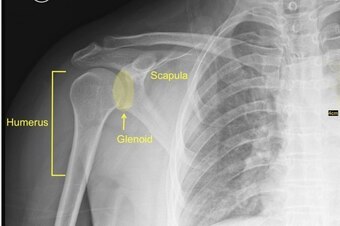

The labrum is a ring of cartilage that encircles the rim of the glenoid—or shoulder socket. It deepens the socket, allowing the head of the humerus—or upper arm bone—to sit more snugly at the point where it meets the shoulder blade.

For a better picture, imagine a golf ball sitting on a tee. The golf ball represents the head of the humerus, and the tee represents the shoulder socket. A shoulder labrum widens and deepens the tee's surface, thereby making it more difficult to knock off the golf ball.